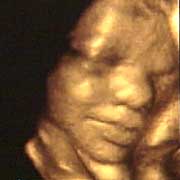

圖文:胎兒子宮內表情豐富 專家稱提供研究新依據

中新網9月13日電 英國天空新聞報道,英國科學家圖亞特·坎貝爾最近利用先進的掃描技術清晰地拍下了孕婦子宮中胎兒的表情,透過他拍攝的照片,人們可以清楚的看到一個尚未降臨世間的小生命喜、怒、哀、樂的表情。

斯圖亞特.坎貝爾是倫敦著名的產科教授,他利用超聲掃描技術拍攝到了胎兒在子宮中打呵欠、眨眼、吮手指、哭泣甚至微笑的畫面,這些都為胎兒行為的研究提供了新的依據,專家認為,這一突破將推動嬰兒健康科學的發展,包括對唐氏綜合癥等嬰幼兒疾病的診治將起到極大的推動作用。

此前,醫學界一直認為,嬰兒要到降生后才可以做出喜、怒、哀、樂的表情,要通過模仿母親才可以學會微笑。

坎貝爾教授說:“有個這種技術,現在許多問題都可以進行研究了。比如說,患有唐氏綜合癥的嬰兒和正常嬰兒的活動方式是否一樣?胎兒是否因為高興才笑?胎兒哭是否是因為在子宮中受到打擾?既然我們都認為子宮內是一片黑暗,那胎兒為什么會眨眼呢?”(章田)